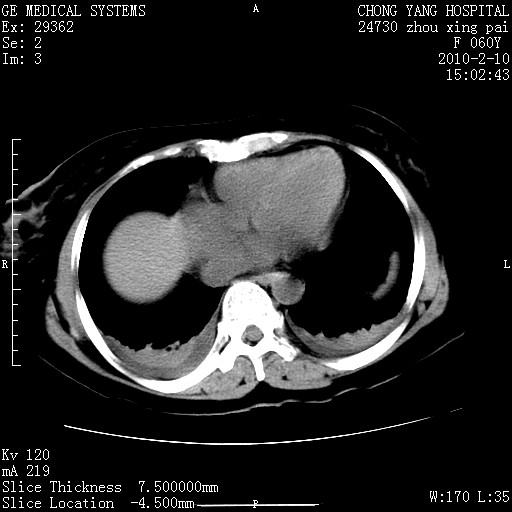

1)胆总管末端梗阻,不排除结石所致可能。2)胰腺炎。3)慢性胆囊炎可能。4)左侧输尿管上段扩张。5)少量腹水。6)双侧少量胸腔积液,伴两下肺部分肺萎陷。

1)胆囊炎。2)胆源性胰腺炎。3)右肾周筋膜增厚,肾旁前间隙积液。4)左侧输尿管上段扩张。5)少量腹水。6)双侧少量胸腔积液,伴两下肺部分肺膨胀不全。

1)胆总管末端梗阻。2)胰腺炎。3)慢性胆囊炎可能。4)左侧输尿管上段扩张。5)少量腹水。6)双侧少量胸腔积液,伴两下肺部分肺萎陷。